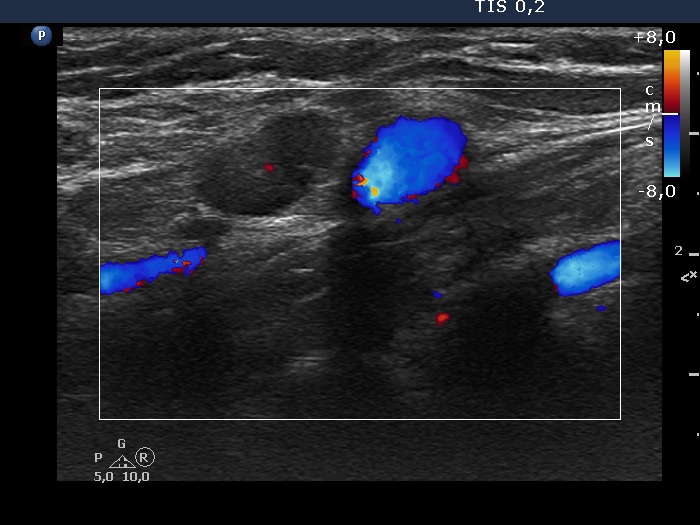

Right lobe, longitudinal scan

Right side of the neck, above the thyroid, transverse scan, color Doppler mode. The vascularization is minimal within this node.